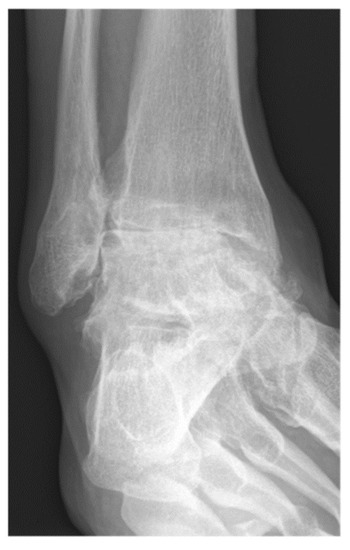

The primary outcome measure was nonunion rate of tibiotalar arthrodesis [2]. Union was defined based on patient reported symptoms and clinical physical examination criteria (no pain, no warmth, improvement in swelling, and stability to stress) and radiographic criteria (visible trabecular bridging across the arthrodesis site and no lucency around the hardware) [40]. Appropriate osseous union was defined as trabecular bridging across the tibiotalar joint (at least 80%) within 6 postoperative months [41] (Figure 3 and Figure 4). In patients with nonunion, computerized tomography (CT) was utilized for further assessment and was evaluated by independent radiologist not involved in any of surgeries. Secondary outcome measures were wound complications, return to the operating room, and rate of development of post-operative deep vein thrombosis (DVT), or pulmonary embolism (PE).

Figure 3.

A 57-year-old male patient presenting complete union of the tibiotar and distal tibiofibular joints at 6 months follow-up.